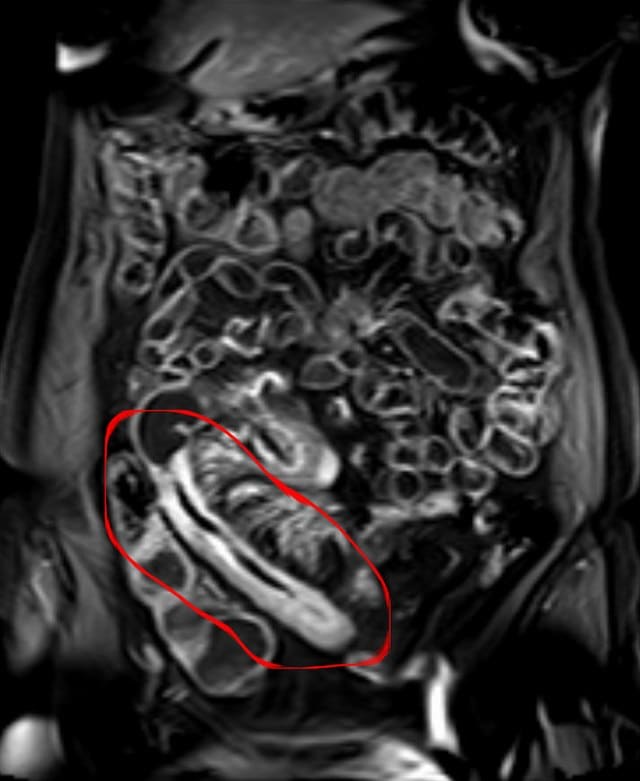

CT 스캔 또는 MRI: 장의 세부 이미지를 얻기 위해 사용됩니다.

진단: 내시경 검사, X-선, MRI, 혈액 검사 등 다양한 방법으로 진단됩니다.